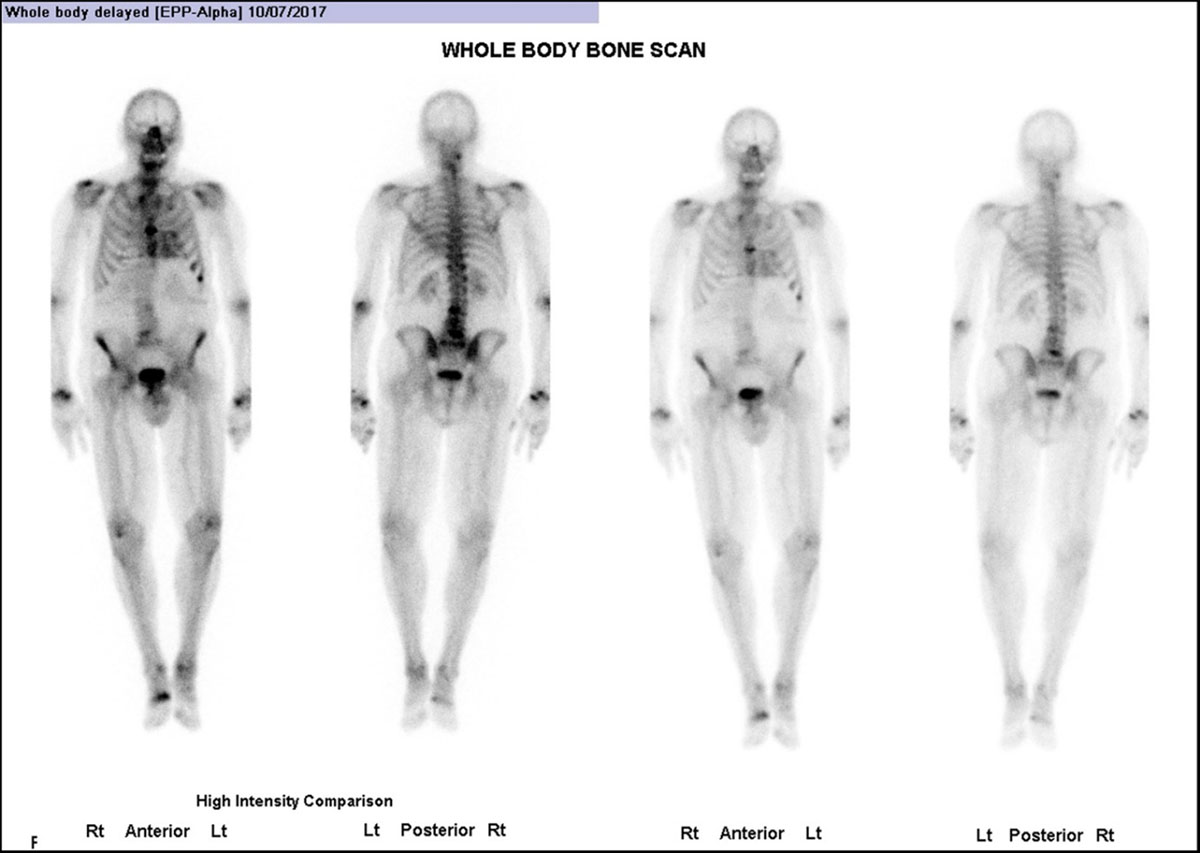

Figure 8

Whole body anterior and posterior planar views (shown at two intensities) performed 3 hours post-injection of Tc99 m HDP, investigating an 85-year-old man with back pain. He had no history of Heart Failure. (Images courtesy of Cabrini Health, Victoria, Australia).